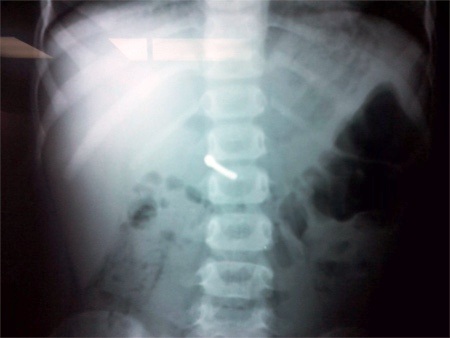

Kết quả X-quang cho thấy chiếc đinh sắt khoảng 3cm trong bụng bé (Ảnh: L.N)

Sau khi được chụp phim, kiểm tra ổ bụng, các bác sĩ bệnh viện này đã phát hiện ở vùng thượng vị của bé có một dị vật dài chừng 3cm, được nhận định là chiếc đinh sắt.